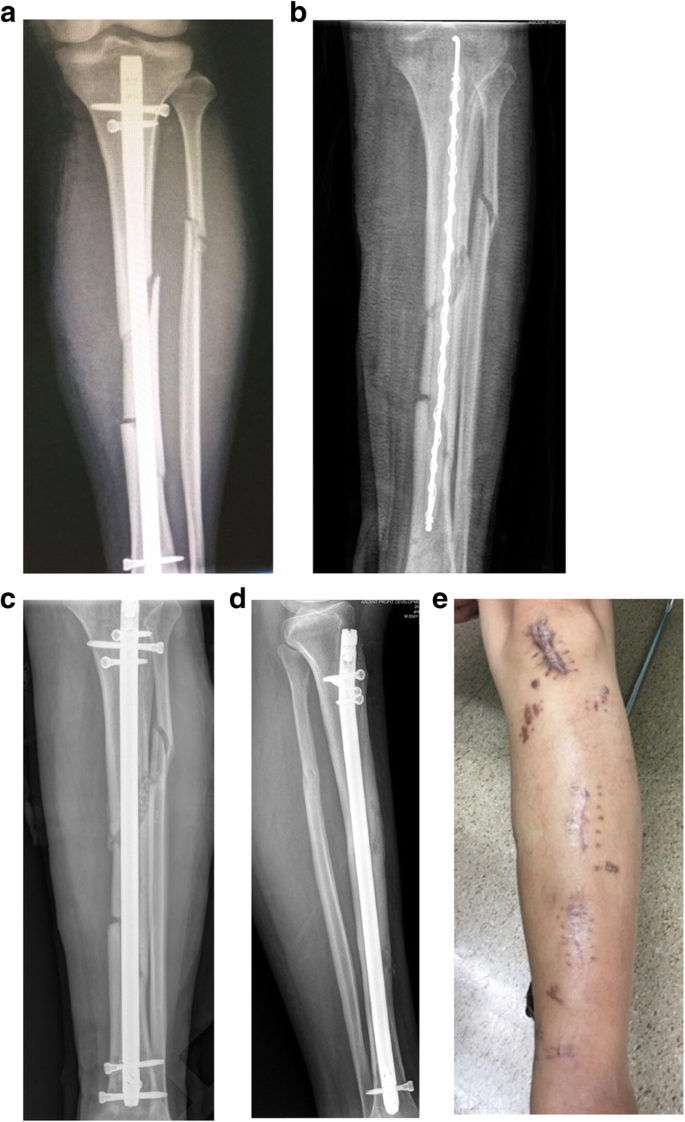

Stable hardware + bone not healed Cierny–Mader 1 type = remove hardware, temporary stabilize + antibiotic cement-coated (ACC) rods, debridement, and reconstruction when clean. a Radiographs of primary internal fixation. b The tibia locking intramedullary nail was removed and replaced by antibiotic cement-coated (ACC) rods. c Reconstruction with locking intramedullary nail with drug delivery system (DDS) when clean. d Radiograph 12 months after treatment. e After 12 months of treatment, the wound was stable